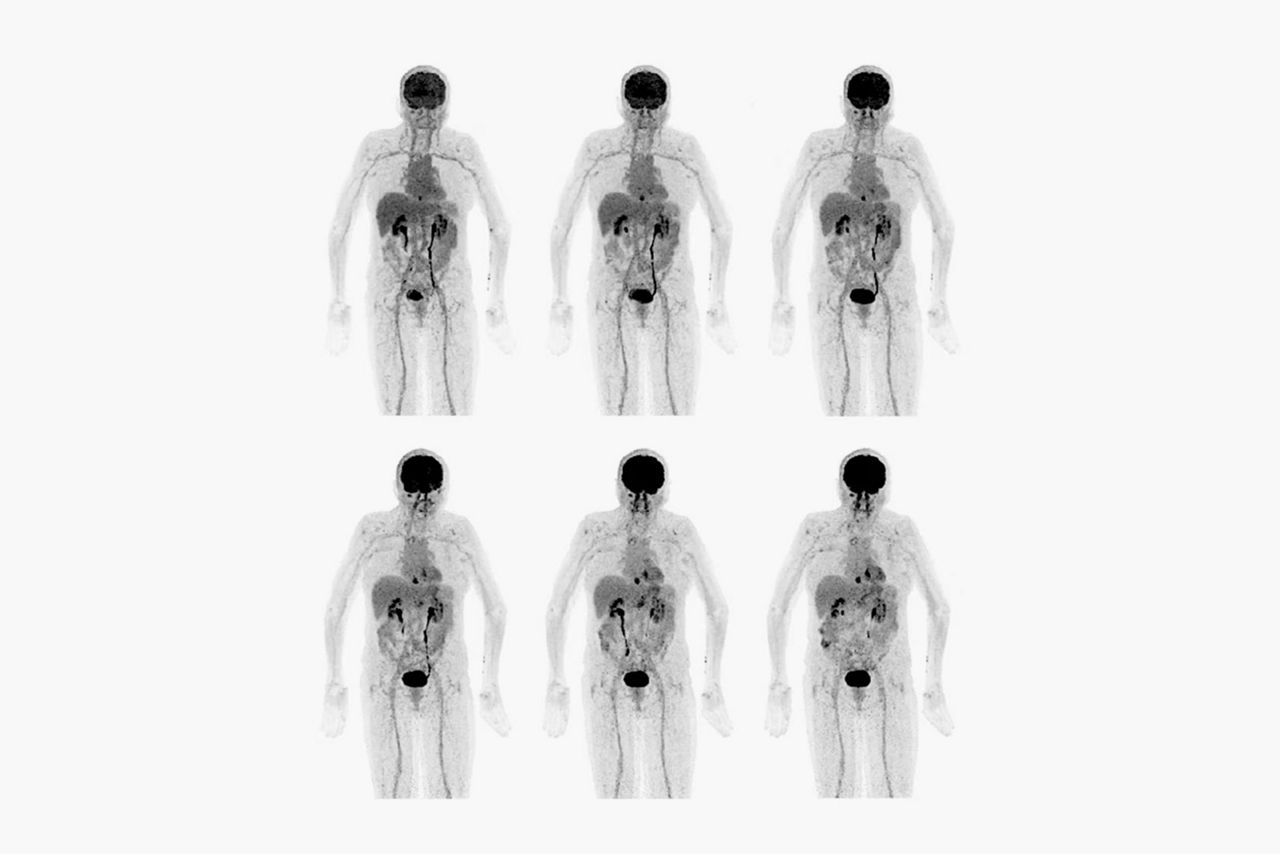

Smaller lesions

Up to a 41% increase in small lesion detectability1

Smaller lesions

Up to a 41% increase in small lesion detectability1